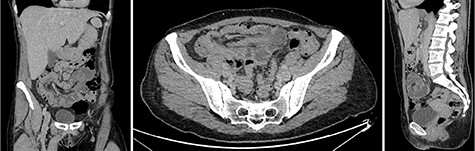

A 51-year-old female patient presented to the emergency department with abdominal pain that started and increased significantly within 1 day. The abdominal pain was described as crampy, appearing first in the periumbilical region with migration to the right lower quadrant. In addition, the patient experienced nausea, but no vomiting and had diarrhea twice that day without blood admixture. The patient’s past medical and family history were unremarkable. In physical examination, the abdomen was non-distended and soft but with rebound tenderness, especially in the right lower and middle quadrant. The rectum was empty and there was no indicator of intestinal hemorrhage. Laboratory tests showed a white blood cell count of 14.5 × 109/L and a C-reactive protein level of 7.0 mg/L. All other studies were within normal limits. An abdominal ultrasound showed a ‘pseudokidney’ sign in the lower abdomen (Fig. 1). Additionally, a computerized tomography (CT) scan of the abdomen and pelvis was performed and revealed an intussusception involving ~20 cm of the ascending and transverse colon (Fig. 2).

Intravenous contrast-enhanced abdominal and pelvic CT scan showed the full extent of the colocolic intussusception. No lead point was evident. (Left) Coronar view with ‘sausage’-shaped lesion. (Middle) Axial view with ‘sausage’-shaped lesion. (Right) Sagittal view with ‘targed’-shaped lesion.